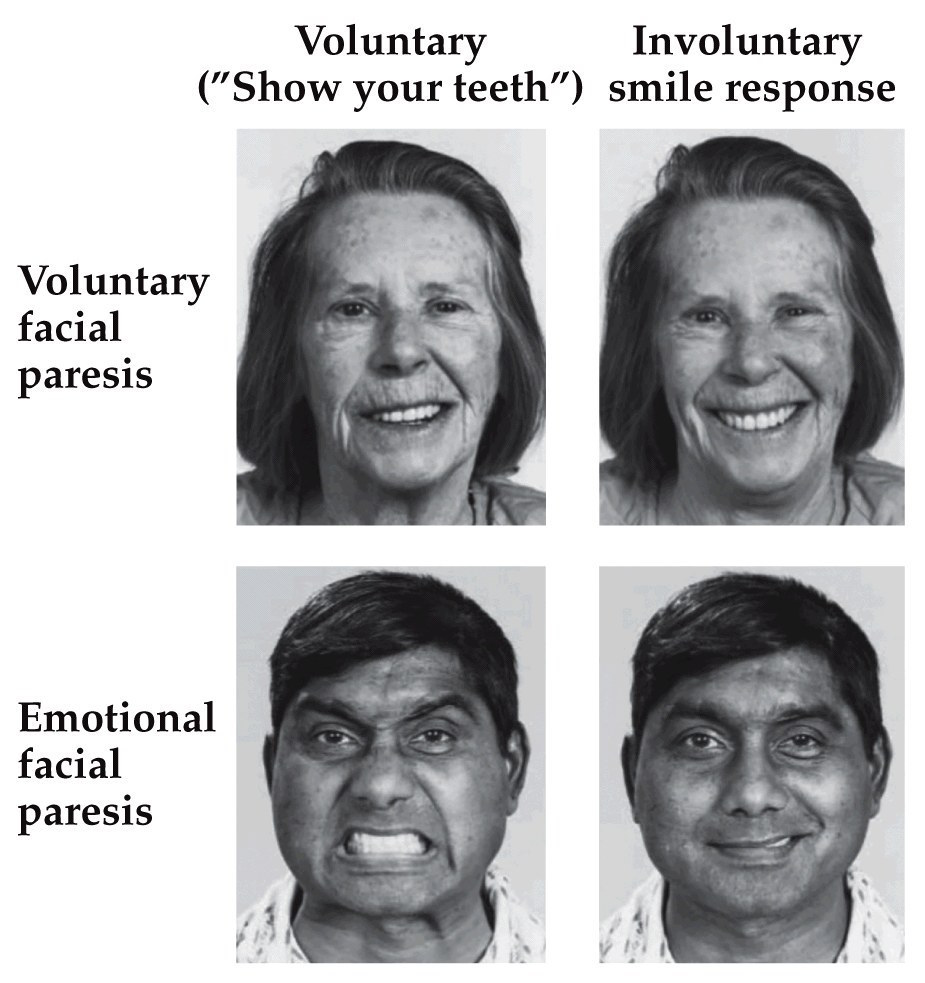

Facial expression of emotion

Two pathways to get to facial muscles that display emotion– voluntary and emotional pathways are separable.

Note:

extrapyramidal system: is a neural network that is part of the motor system causing involuntary movements

pyramidal pathways (corticospinal and some corticobulbar tracts) may directly innervate motor neurons of the spinal cord or brainstem

extrapyramidal system centers on the modulation and regulation (indirect control)

Extrapyramidal tracts are chiefly found in the reticular formation of the pons and medulla, and target neurons in the spinal cord involved in reflexes, locomotion, complex movements, and postural control

paresis: muscle weakness

- Both a volitional (with deliberate action) and a non-volitional component. Are in separate pathways. Both pathways ultimately lead to motor neuron pools that activate muscle contraction or smooth muscle/gland secretions